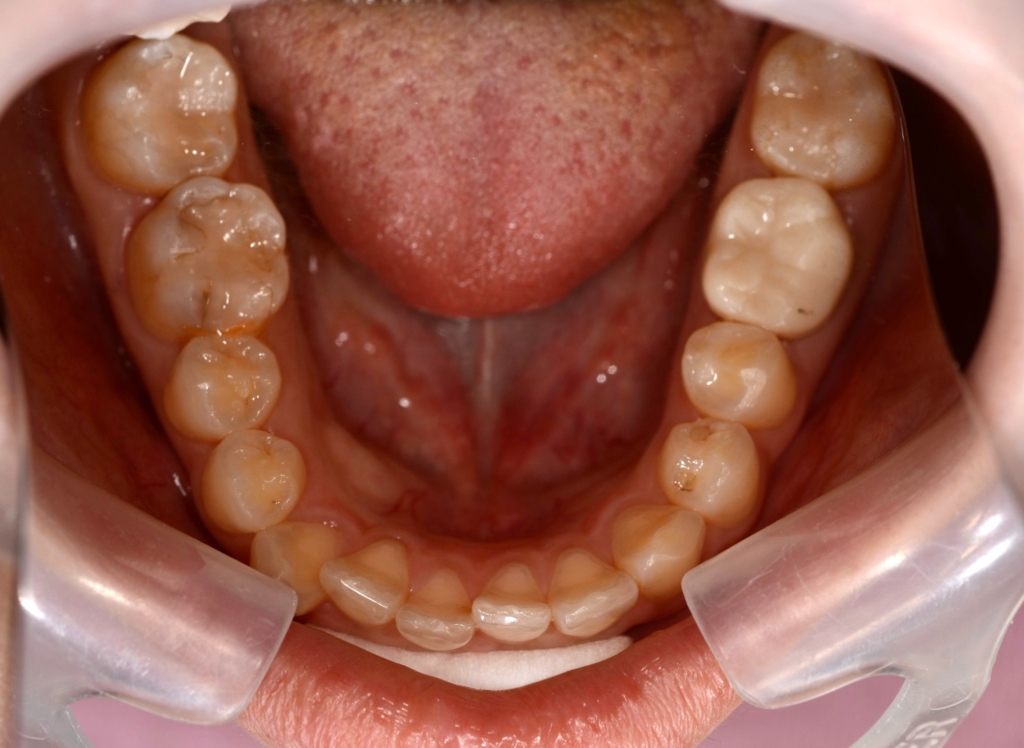

【After】

変な悪目立ちをするものはありません

矯正後の状態をレントゲン写真で確認すると、